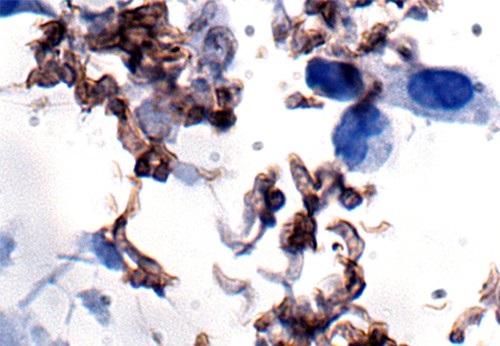

Sleeping sickness - known formally as African trypanosomiasis - is transmitted through the bite of the tsetse fly and threatens tens of millions of people in sub-Saharan African countries. After entering the body, the parasite delivered by the fly causes such symptoms as inverted sleeping cycles, fever, muscle weakness, and itching. The parasite eventually invades the central nervous system and, depending on its type, can kill its host in anywhere from a few months to several years.

The study is the second recent collaborative effort between Dr. Luisa Figueiredo at the University of Lisbon in Portugal and Dr. Takahashi, who holds the Loyd B. Sands Distinguished Chair in Neuroscience. It builds upon research they published last year that showed for the first time that parasites have biological clocks. The study further revealed that this circadian cycle renders the sleeping sickness parasite - known as Trypanosoma brucei - more vulnerable to medications during the afternoon.